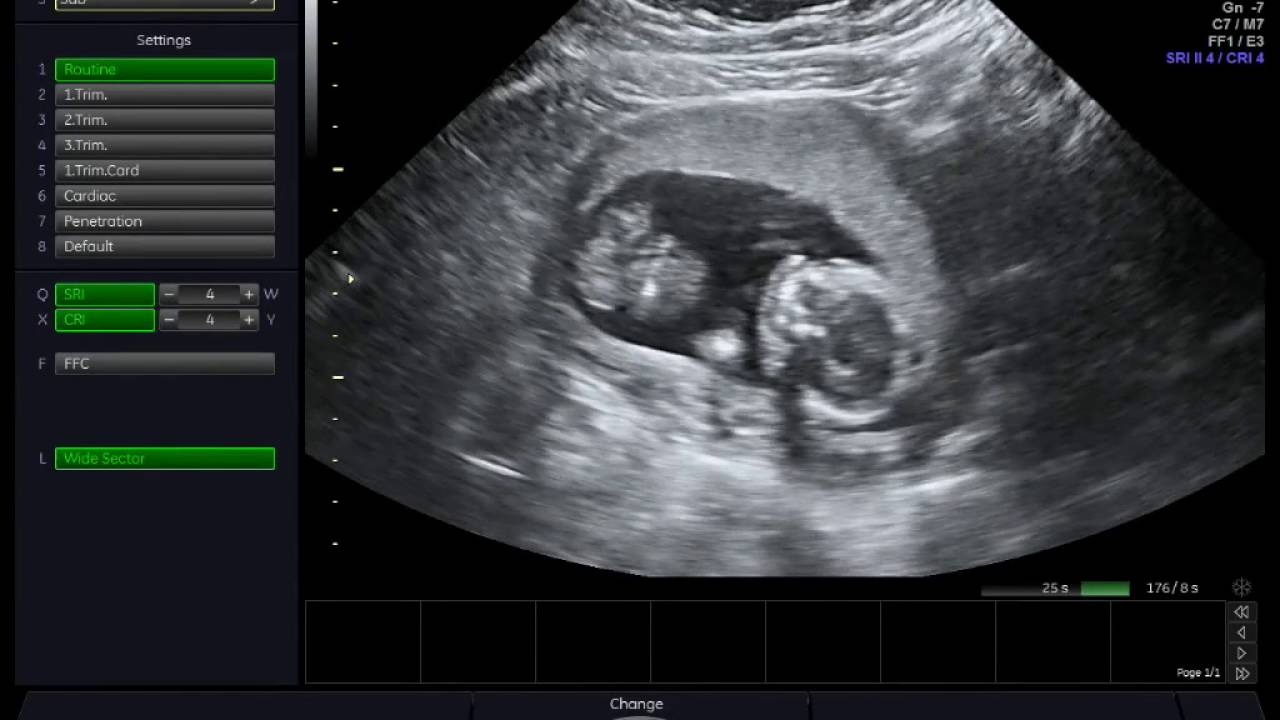

Qua hình ảnh siêu âm, mẹ bầu có thể nhận thấy có thêm cả sự thay đổi ở kích thước thai 16 tuần. Ở các tuần trước, phần đầu thường to hơn phần thân nhưng sang đến tuần này, kích thước phần đầu so với thân đã dần cân đối hơn. Đốt sống cổ dần hình thành và phát triển, hỗ trợ phần đầu thai được nâng lên cao hơn.

Khi theo dõi kết quả siêu âm, bác sĩ sẽ cho người mẹ biết được giới tính thai nhi. Như vậy, có thể nói, việc xác định thai nhi tuần thứ 16 là trai hay gái là hoàn toàn có thể. Tuy nhiên, trong một vài trường hợp, hình ảnh siêu âm không hiện lên bộ phận sinh dục của bé do tư thế nằm không thuận lợi. Tỷ lệ này chỉ khoảng dưới 20%.

Hình ảnh siêu âm thai nhi 16 tuần tuổi hiện nay đã được cải tiến với chất lượng tốt hơn, có thể cung cấp cho mẹ biết những thông tin sau.

Bước sang tuần thai thứ 16, bộ phận sinh dục của bé đã hình thành đầy đủ. Với công nghệ siêu âm 4D và sự hỗ trợ của bác sĩ, ba mẹ có thể quan sát bộ phận này trên hình ảnh siêu âm.